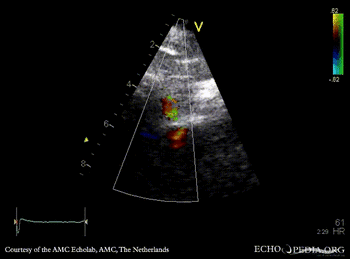

| A4CH: coronary fistula | Pulsed-wave signal of flow through coronary fistula |